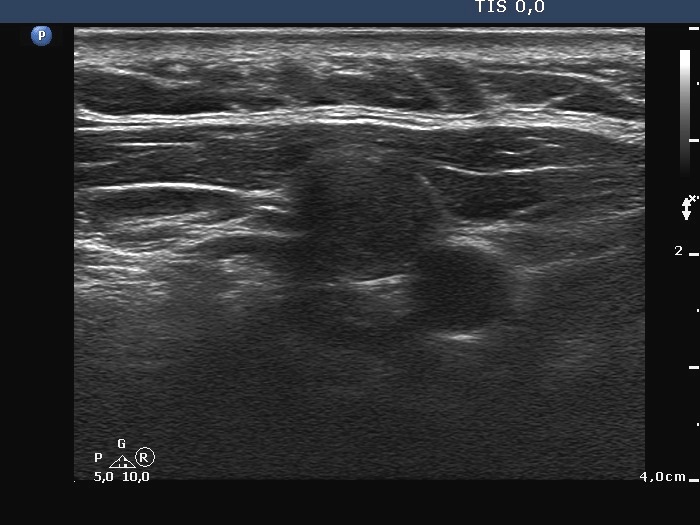

Ultrasonography: there was no parenchyma in the thyroid beds. Lateral to the right lobe there were several enlarged lymph nodes.

Cytological diagnosis: medullary carcinoma.